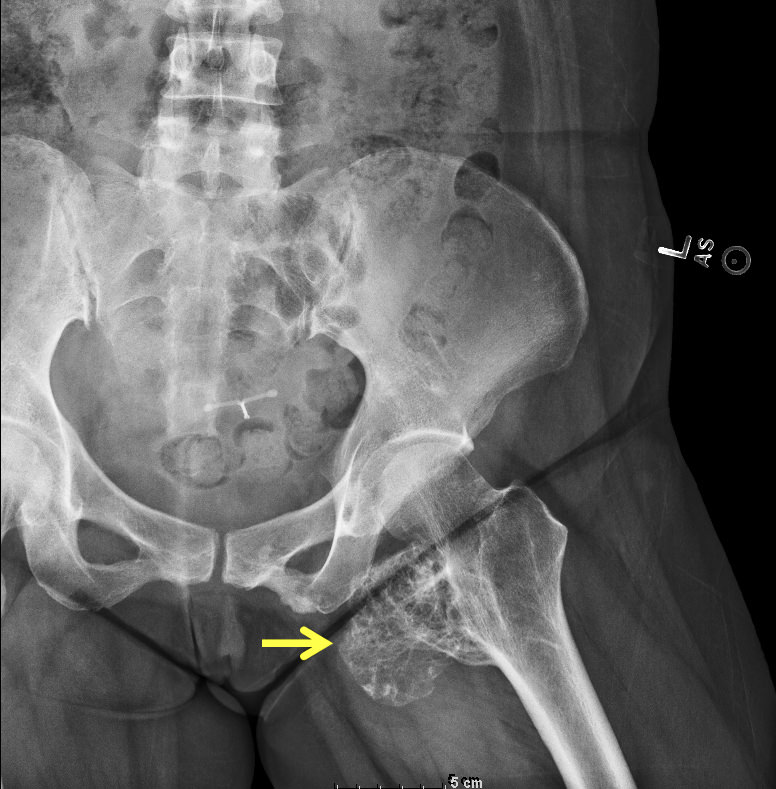

Radiology description

- Pedunculated or sessile

- Mature bony stalk continuous with the cortex; cancellous bone of stalk communicates with that of underlying bone

- Thin, lobulated cartilaginous cap, which may contain calcifications

- Growth perpendicular to the long axis of the bone

Radiology images